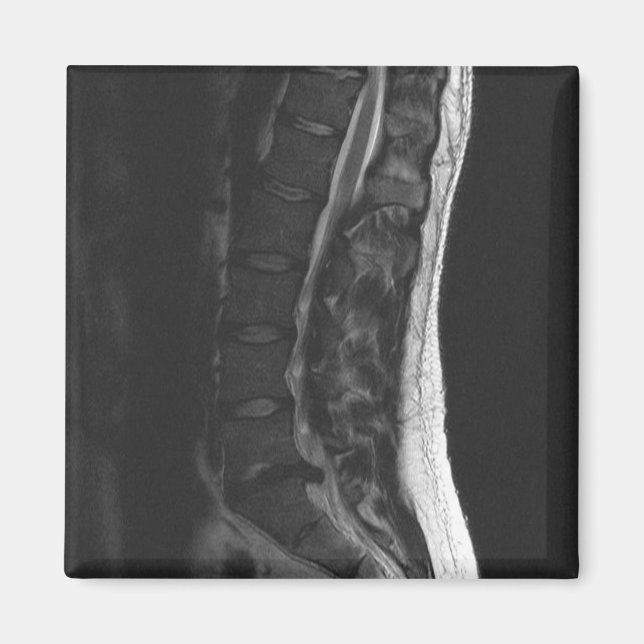

Magnet de disque en série

J'ai transformé mon IRM en aimant frigo ! Ceci montre mon disque L5-S1 qui a été rompu. Il me rappellera toujours d'utiliser une posture correcte et de se plier à genoux! Ne laissez pas ça vous arriver... J'ai eu deux opérations pour le corriger.